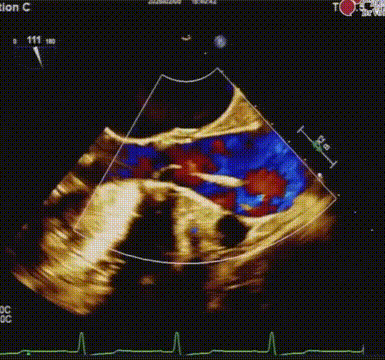

心脏超声示:

重度主动脉瓣狭窄合并中度反流,EF: 46%,AV MPG: 57 mmHg,AV 4.9 m/s,LVIDd: 54 mm。

释放后造影及超声评估瓣膜活动良好,轻度瓣周漏;

瓣膜释放后食道超声评估

经食道超声提示瓣膜位置、形态及功能满意,未见明显反流,瓣周漏较前好转,微量瓣周漏,复查造影瓣周漏明显减少至微量,左右冠脉无阻塞,人工瓣膜植入深度约:无冠窦侧为1mm,左冠窦侧为3mm。复查左心室及升主动脉收缩舒张压分别为157/9mmHg、154/71mmHg。手术取得圆满成功。

术后食道超声评估